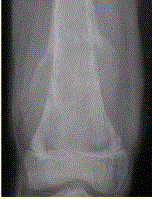

问题 患者男,16岁,左大腿下部疼痛伴肿胀2个月,逐渐加重。自感左膝上方胀痛,尤以夜间为著,伴行走困难。既往史及家族史无特殊。查体:左大腿下部明显肿胀,皮温较对侧升高。碱性磷酸酶明显增高。股骨平片及MRI见下图。 关于此病变的定位,正确的是

选项 A.病变主体位于左股骨下端骨骺,累及干骺端 B.病变主体位于左股骨下端干骺端,累及骨骺 C.病变主体位于左股骨远侧骨端 D.病变主体位于左股骨下端周围软组织,骨质受累 E.病变主体位于骨髓质,皮质受累 F.病变主体位于骨皮质,髓质受累

答案 BE